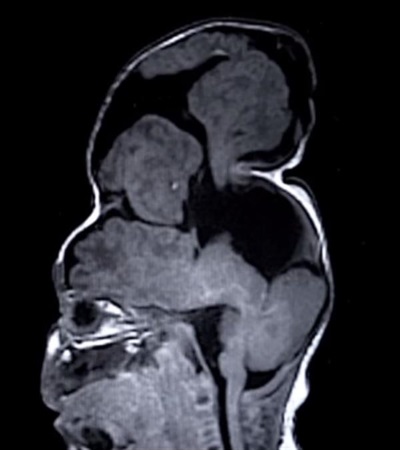

准父母Sierra和Dustin Yoder被告知他们未出世的孩子——Bentley,患有一种称为“脑膨出”(亦叫做颅裂)的罕见疾病。在进行常规的超声波检查时,医生们发现Bentley的大脑从头骨的缝隙中突出,医生们判断:Bentley很可能无法长时间生存,即使可以,他的大脑也不能正常工作。

Bentley在四个月大时被父母带到克利夫兰诊所,那里的医生认为Bentley使用的大脑的确是突出的那部分,并且将膨出部分塞回头颅内是一个全能的、艰巨的任务。Sierra和Dustin Yoder再次去波士顿儿童医院约见了当时负责诊断Bentley病症的John Meera博士团队,他们发现,Bentley大脑中的膨出部分有认知功能、解决问题功能和视觉功能,因此不能被摘除,只能将它再次塞回颅内。

由于手术的复杂性,波士顿儿童医院的外科医生需要为他们的手术计划聘请“外援”——3D打印技术。通过大脑扫描得到的可视数据,再用3D打印Bentley的头骨模型,这可以让外科医生能够在做手术之前,用一个3D打印的塑料复制品进行术前准备。3D打印头骨决定了Bentley颅内能被塞回多少膨出部分。